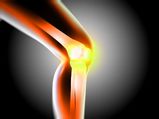

Football For 3 Hours A Week Boost's Bone Growth In Teenagers - Finds Study

Obesity, Weight Loss In Adolescence May Cause Permanent Bone Loss

Teenage Diabetes Is An Ever-increasing Risk: How To Make Youngsters Take Care Of Their Health?